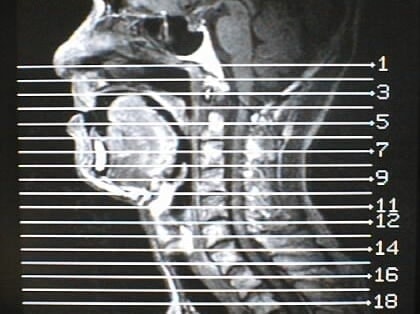

MRI画像比較

中咽頭末期がんMRI画像①

入院当時MRI画像①

中咽頭末期がん消滅時MRI画像①

入院3か月後癌消滅MRI画像①